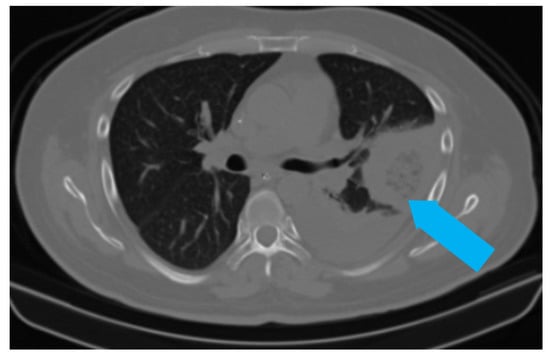

5.1. Role of Diagnostic Imaging

Diagnostic imaging is vital for early detection of invasive mucormycosis in patients with clinical suspicion. Certain distinguishing features of the lung parenchyma on a CT scan of the chest in patients with PM include multiple pulmonary nodules, often pleural-based, presence of lung cavitations and effusions (Figure 1, Figure 2, Figure 3 and Figure 4) [23]. The ‘reverse halo sign’ (central ground glass opacity surrounded by dense consolidation) is highly appreciated, mainly in neutropenic leukemic hosts. In a recent systematic review of CT findings in 16 patients with proven CAPM, consolidation and cavitation were seen in 11 (69%) patients, pleural effusion in 7 (47%), pneumothorax and nodules in 3 (19%) and ‘reverse halo sign’ and pulmonary embolism was seen in 2 (13%) patients [24]. Previously, Nam et al. reported that in hematologic patients, while consolidation and nodules are seen earlier in the disease process, central necrosis, cavitation and the air crescent sign are late findings [25]. This would suggest that CAPM is either under-diagnosed due to lack of differentiation from other fungal, including aspergillosis or bacterial pneumonias, or is diagnosed much later in the illness.

Figure 1. Chest radiograph (AP view) of patient showing round opacity in left lung (blue arrow).

Figure 2. CT scan of the same patient showing a pleural-based consolidation with central clearing (blue arrow) and surrounding, denser, consolidation typical of reverse halo sign; also seen in left mild pleural effusion.